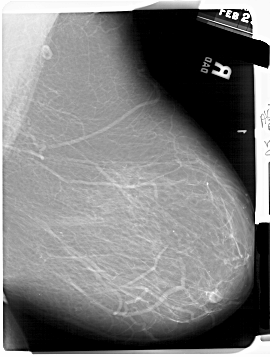

A_1701_1.RIGHT_MLO

RIGHT_MLO LINES 6766 PIXELS_PER_LINE 5116 BITS_PER_PIXEL 12 RESOLUTION 43.5 NON_OVERLAY